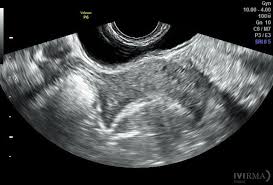

Finalmente, el desarrollo de la ecocardiografía transesofágica (ETE) e intravascular representó un cambio significativo en la manera en que se pueden obtener imágenes del corazón y los vasos sanguíneos. La ecocardiografía transesofágica implica el uso de un transductor colocado en el esófago, lo que permite obtener imágenes de alta resolución sin la interferencia de los pulmones o la pared torácica. Esta modalidad es particularmente útil para la evaluación de estructuras cardíacas en pacientes con una anatomía difícil de evaluar con ecografía transtóracica, como en el caso de la visualización de las aurículas, las válvulas y la aorta.

El trabajo de estos investigadores permitió superar las limitaciones de las sondas mecánicas, al integrar transductores electrónicos más pequeños y precisos que se podían insertar a través del esófago, ofreciendo imágenes claras del corazón sin la interferencia de la pared torácica, las costillas o el pulmón. Las imágenes obtenidas mediante este enfoque eran especialmente útiles para el estudio de patologías cardíacas complejas que no podían ser evaluadas adecuadamente con las técnicas ecocardiográficas tradicionales.